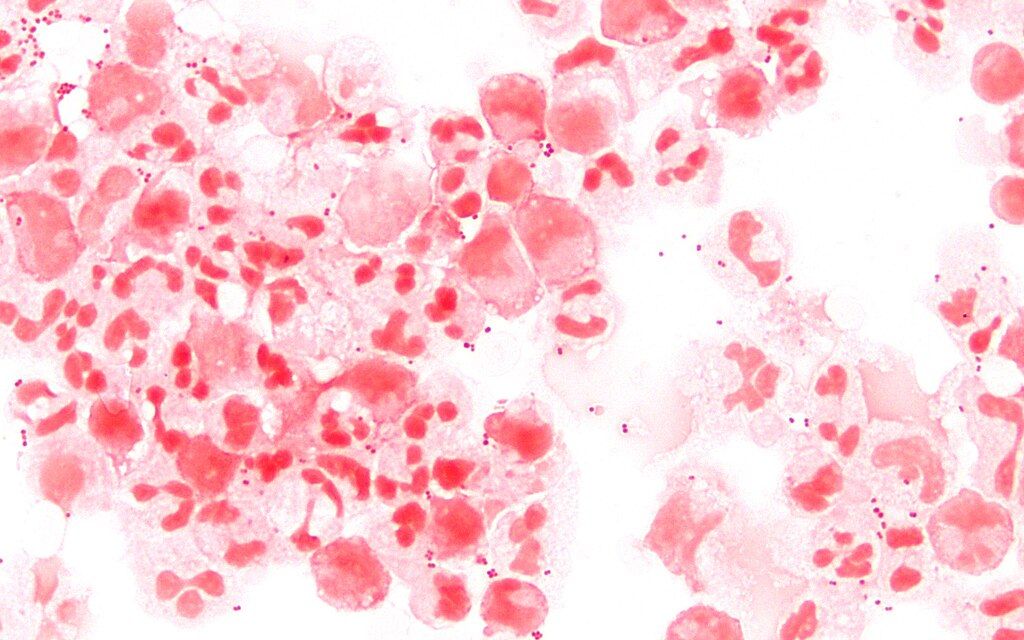

Inwazyjna choroba meningokokowa najczęściej przebiega pod postacią sepsy z zapaleniem opon mózgowo–rdzeniowych lub samej sepsy. Wywołuje ją bakteria – Neisseria meningitidis – potocznie nazywana meningokokiem.

– Ryzyko zachorowania u najmłodszych dzieci wynika z niedojrzałości ich układu odpornościowego. W przypadku starszaków dodatkowym czynnikiem jest przebywanie w zamkniętych środowiskach, takich jak przedszkola czy żłobki. Bliski kontakt między dziećmi sprzyja zakażeniom. W takich placówkach nawet do 80% osób może być nosicielami meningokoków – podkreśla dr n. med. Alicja Karney i dodaje – Objawy choroby meningokokowej mogą być różne. Wystąpić może gorączka, złe samopoczucie, niechęć do jedzenia i picia, przyspieszony oddech, zaburzenie świadomości Wysypka wybroczynowa, nieblednąca pod naciskiem to bardzo wyraźny, chociaż nie zawsze występujący, sygnał alarmowy oznaczający potrzebę pilnej interwencji medycznej.